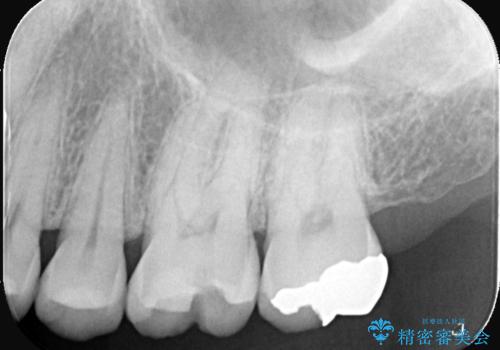

- 主訴:銀の詰め物が外れてしまった

保険適応のメタルインレーが脱離し、中が少し虫歯になっていたため審美性も良いセラミックインレーでのやり替えとなりました。

旧インレー窩洞内のカリエスと裏層を除去し、新たにCR裏層したうえでセラミックインレー修復を行いました。セラミックインレーセット時は、ラバーダム防湿を行っています。